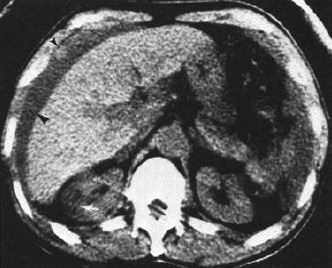

図13. CTの世代による画質の進歩.

いずれも前頭葉髄膜腫の症例.(左)1973年,第1世代CT(EMI)[4].(中)1980年,第2世代CT(EMI 1010)[5].(右) 1990年,第3世代CT (GE CT/T 8800)[5].着実な画質の進歩がわかる.